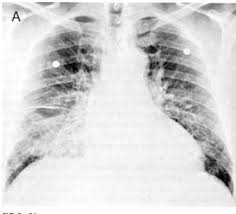

Η αρχική προσέγγιση ασθενών με πνευμονικό οίδημα συμπεριλαμβάνει ΗΚΓφημα και ακτινογραφία θώρακος. Στο ΗΚΓφημα μπορεί να περιέχονται ευρήματα μυοκαρδιακής ισχαιμίας, αρρυθμίας, διαταραχές αγωγιμότητας, όπως κολποκοιλιακός αποκλεισμός και αποκλεισμός σκέλους, κύματα Q ενδεικτικά παλαιότερου ΕΜ ή κριτήρια διαγνωστικά υπερτροφίας, ενώ ευρήματα διαγνωστικά υπερτροφίας μπορεί να παρέχουν κλείδες αναφορικά με το αιτιολογικό υπόστρωμα της καρδιακής ανεπάρκειας. Η διάταση του κόλπου είναι συμβατή με χρόνια αύξηση της πιέσεως πληρώσεως. Από την ακτινογραφία θώρακος αναγνωρίζουμε αναστροφή της αιματικής ροής και επαναδιανομή της αιματώσεως, με ή χωρίς αμφοτερόπλευρες διηθήσεις, κλασικά περιπυλαίες, όπως και καρδιομεγαλία. Μπορεί να αναγνωριστεί πλευριτική συλλογή, εύρημα, γενικά με χαμηλή ειδικότητα κι ευαισθησία. Από τα εργαστηριακά ευρήματα περιλαμβάνονται ηλεκτρολύτες ορού και κρεατινίνη, γλυκόζη αίματος για την αναγνώριση υποκείμενου σακχαρώδους διαβήτη, ηπατικό έλεγχο, που μπορεί ανν αποκαλύπτει ηπατική συμφόρηση, κια πλήρη αιματολογικό έλεγχο, εφόσον η αναιμία μπορεί να παροξύνει τη χρόνια συμφορητική καρδιοπάθεια. Η μέτρηση του κολπικού νατριουρητικού πεπτιδίου,BNP, έχει εισαχθεί στον αλγόριθμο της χρόνιας καρδιακής ανεπάρκειας. Το ΒNP παράγεται από κοιλιακά μυοκύτταρα σε απάντηση της επιτάσεως του stress του τοιχώματος (αύξηση της πιέσεως πληρώσεως και stretch). Τα επίπεδα του ΒNΡ στο πλάσμα αυξάνονται επί καρδιακής ανεπάρκειας και οι συγκεντρώσεις του στο πλάσμα συσχετίζονται με τη λειτουργική τάξη, κατά ΝΥΗΑ. Οι μετρήσεις του ΒΝΡ χρησιμοποιούνται μεταξύ της καρδιακής και της πνευμονικής αιτιιολογίας της δύσπνοιας. Στη μελέτη breathing not Properly, BNP, μετρήθηκε το ΒΝΡ πλάσματος με μια ταχεία μέθοδο σε 1856 ασθενείς που προσήλθαν στα ΤΕΠ με κύριο αίτημα δύσπνοια και διαπιστώθηκε ότι 47% διαγνώστηκαν με χρόνια καρδιακή ανεπάρκεια και 49% μη καρδιακής αιτιολογίας δύσπνοια. Στο 5% διαπιστώθηκε ότι είχαν μη καρδιακής αιτιολογίας δύσπνοια, με δυσλειτουργία, όμως, της αριστερής κοιλίας. Οι συγκεντρώσειος ΒΝΡ, μεγαλύτερες των 400 pg/ml υποδηλώνει, με ακρίβεια, καρδιακή ανεπάρκεια. ενώ επίπεδα χαμηλότερα των 100 pg/ml επιβεβαιώνει τη μη καρδιακής αιτιολογίας δύσπνοια. Τιμές μεταξύ 100-400, είναι λιγότερο χρήσιμες. Παρόμοιες τιμές μπορεί να αντανακλούν χρόνια καρδιακή ανεπάρκεια, αλλά και προϋπαρχουσα δυσλειτορυγία της αριστερής κοιλίας ή δεξιά καρδιακή ανεπάρκεια. Η προσθήκη υπερηχοκαρδιογραφήματος σε συνθήκες ισχιμαίας μπορεί να είναι ιδιαίτερα χρήσιμη στην εκτίμηση ασθενών με ενδιάμεσες τιμές ΒΝΡ.